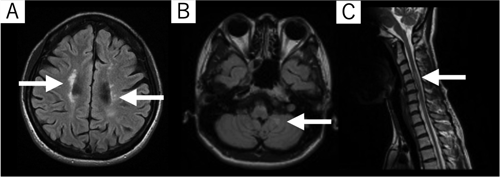

症例は,X年Y月Z日に急性増悪した多発性硬化症の40歳代女性(初発:X−3年)であった。家族は夫と子供の4人家族で,病前は育児や家事,週5日の就労を行っていた。増悪前は補助具なし歩行が可能も,Z日より徐々に身体機能低下を認め,Z+5日には歩行器歩行レベルに低下し前医に入院となった。Z+5日の画像所見ではMagnetic Resonance Imaging(MRI)のFluid Attenuated Inversion Recovery(FLAIR)画像にて,脳室周囲や左小脳,脊髄(C4周囲)に高信号域を認めた(図1)。薬物療法は,Z+5~8日にIVMP(ソル・メドロール500 mg×2/日静注),Z+9~32日に経口ステロイド療法(プレドニン錠,50 mg/日にて開始し,Z+32日に終了)が施行された。前医でのリハビリテーションはZ+7日より開始され,Z+27日に右片ロフストランド杖と,左オルトップ型短下肢装具(Ankle-foot Orthosis. オルトップ®,パシフィックサプライ株式会社,日本:以下,オルトップAFO)で自宅退院となった。その後,Z+30日より十勝リハビリテーションセンター外来リハビリテーションが開始となった。

脳室周囲(A),左小脳(B),脊髄C4周囲(C)に高信号域(白矢印)を認めた.

MRI: Magnetic Resonance Imaging, FLAIR: Fluid Attenuated Inversion Recovery.